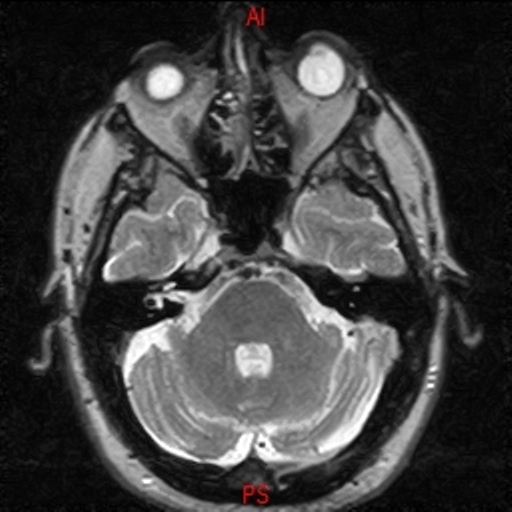

• Resonancia NORMAL CRANEAL T2 AXIAL

• Resonancia NORMAL CRANEAL T1 AXIAL